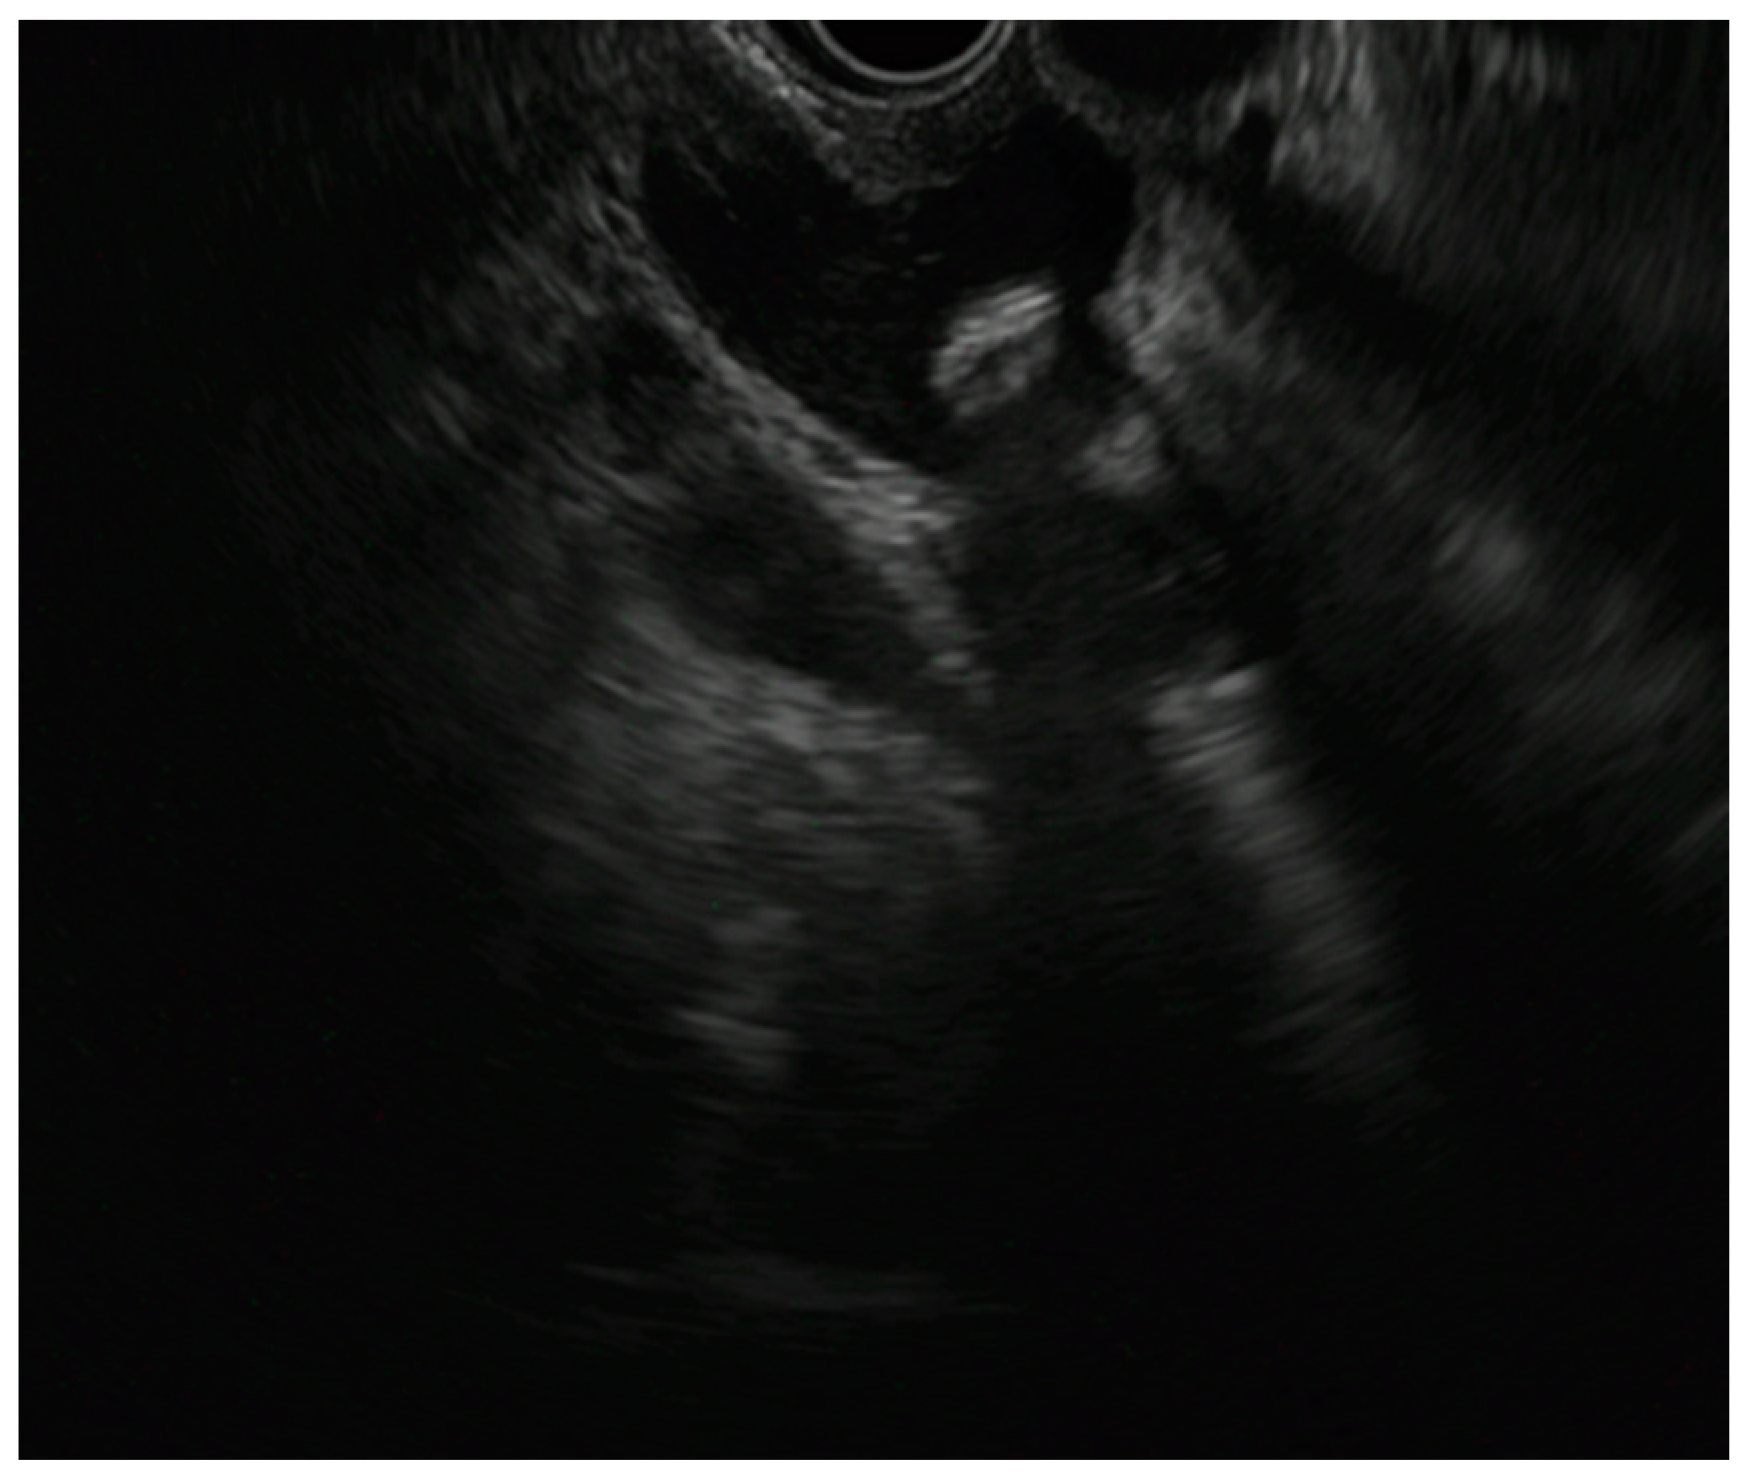

Figure 2. Please revise as Endoscopic ultrasound-guided gallbladder drainage (EUS-GBD) with first flange opening of the elctrocautery lumen-apposing metal stent (EC-LAMS).

The initial documentation of EUS-GBD can be traced back to 2007, marking the first recorded account of this procedure. This was a case of acute cholecystitis (AC), associated with an unresectable hilar cholangiocarcinoma deemed unfit for surgery, that was treated with the placement of two DPS into the gallbladder with a trans-duodenal approach [32]. Over the years, EUS-GBD underwent technical refinement that minimized the risk of bile leakage and stent migration due to the difficulty in obtaining apposition of the gallbladder and the gastrointestinal wall, thus growing in popularity and widespread application. The first implementation of the technique came from the use of anti-migration tubular SEMS over plastic stents [33,34], followed by the development of LAMS [35] and subsequently EC-LAMS [36]. Currently, the most common indication for EUS-GBD is represented by AC in patients unfit for cholecystectomy [37]. Studies in this population showed that EUS-GBD is a safe and effective technique, with fewer AEs, reinterventions, readmissions and episodes of recurrent cholecystitis, when compared to percutaneous trans-hepatic gallbladder drainage (PT-GBD) [38,39,40,41]. According to these data, ESGE recommends EUS-GBD over PT-GBD for patients with AC at high surgical risk [42]. Furthermore, EUS-GBD can be performed to internalize a previously placed PT-BGD in patients unfit for cholecystectomy, in order to create definitive drainage with encouraging success rates and very limited AEs during the follow-up [43]. The other main indication of EUS-GBD is as a rescue approach for the drainage of patients with DMBO after failed attempts at both ERCP and EUS-BD, which occur in a very small proportion of patients (around 0.1%), as an alternative to performing PTBD [11,42]. While failure of ERCP can be due to various causes, such as altered papillary anatomy, duodenal stenosis or altered post-surgical anatomy [44,45], failure of EUS-BD could be due to reasons such as lack of visualization of the site for biliary access, insufficient dilation of CBD, the interposition of vessels or a distance between the CBD and duodenal wall of more than 10 mm due to tumor infiltration or the presence of a great amount of ascites [46]. EUS-GBD, conceptually similar to a surgical anastomosis [47,48], aims at providing BD through the cystic duct in the case of DMBO. Therefore, cystic duct patency should be assessed accurately before drainage with cross-sectional imaging and a good diagnostic EUS [42,49,50]. To perform an EUS-GBD, a LAMS is placed within the gallbladder to create an anastomosis with either the stomach (cholecystogastrostomy) or the duodenum (cholecystoduodenostomy); moreover, in case of post-surgical anatomical variants the jejunum can be chosen as site of drainage (cholecystojejunostomy) [51]. [Figure 2].